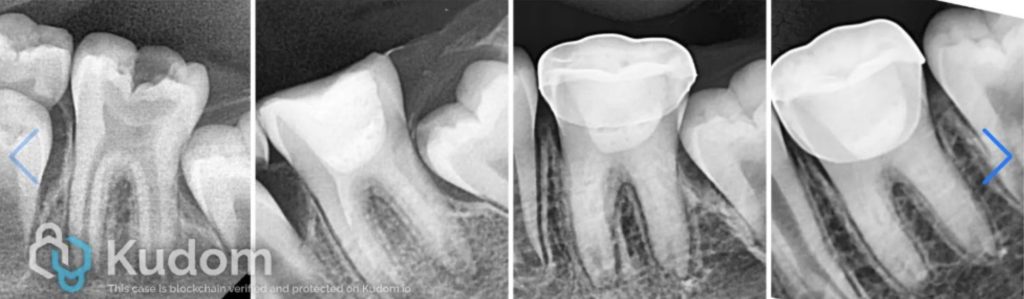

Fig. 1

Xray Shows deep carious lesion in tooth 36. The root length is nearly complete with wide open apical foramina and indistinct apical lamina dura around both mesial and distal roots.

Fig. 2

Xray shows the placement of calcium hydroxide medicament in the canals.